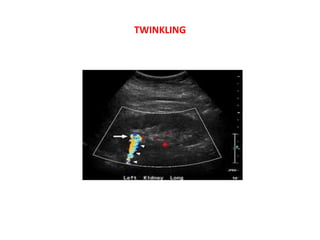

8) Twinkling artifact

Twinkling artifact is seen with (CFD) colour flow Doppler

ultrasound . It occurs as a focus of alternating colours on

Doppler signal behind a reflective object (such as a calculus),

•

It appears with or without an associated colour comet-tail

artifact

The underlying mechanism is thought to be a result of

inherent noise within the US scanner, specifically phase

(a.k.a. clock) jitter within the Doppler electronics .

Twinkling artifact is more sensitive for detection of small

stones (e.g. urolithiasis, cholelithiasis) than is acoustic

shadowing. It is most pronounced when the reflecting surface

is rough and highly dependant on machine setting

@ when the focal zone is located below a rough reflecting

surface, the twinkling artifact becomes more obvious than

when it is above it.

@ decreased pulse repetition frequency facilitates better

visualisation of the artifact.

@ The presence of renal twinkling artifact on sonography has

a high positive predictive value (78%) for the presence of

nephrolithiasis as unenhanced CT.